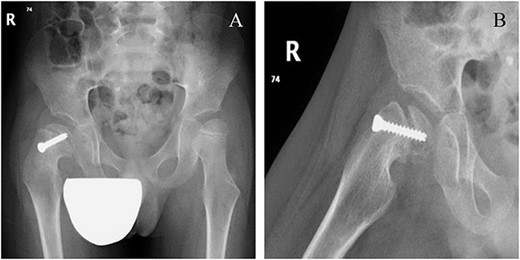

A 5-year-old independent ambulatory Middle Eastern boy with CP who was born preterm and developed grade III intraventricular haemorrhage and periventricular leucomalacia and was on AEDs, including valproic acid (VPA) and levetiracetam (LEV), for >3 years and was controlled over the last year (no history of seizure attack) presented to the emergency room (ER) with right hip pain and inability to bear weight for 4 weeks; the patient had no history of fever or trauma. Physical examination shows a thin, the weight is 12 kg, the height is 101 cm, vital signs within the normal range, tenderness over the right hip, and external rotation of the right hip, with restricted hip mobility. A radiological study was performed ~3 months before the patient presented to the ER for follow-up examination of a left hip coxa valgus deformity with no apparent abnormalities in the right hip (Fig. 1). Initial imaging studies conducted in the ER showed an anterior–posterior view of the pelvic radiograph, revealing Klein’s line [13] not intersecting the capital femoral epiphysis (Fig. 2), and frog-leg lateral view radiograph of the right hip (Fig. 3) confirmed SCFE and Southwick’s slip angle [13] of ~50° (moderate). Laboratory findings were clear for endocrine and renal diseases or infection, except for low vitamin D (total 25-OH Vitamin D: 43.4 nmol/L), suggesting vitamin D insufficiency. The diagnosis was confirmed with clinical and radiological studies as right-sided unstable SCFE requiring surgery. Surgical intervention was performed with percutaneous in situ fixation using a single fully threaded 4.5-mm cannulated screw (Fig. 4). Postsurgical rehabilitation included non-weight-bearing right lower extremities for 6 weeks. Regular follow-up with serial radiology studies showed stable fixation with no migration of screw or further slippage at 6 weeks (Fig. 5) and 3 (Fig. 6), 15 (Fig. 7), and 36 months (Fig. 8). During follow-up, a painless range of motion in the right hip was observed, with full weight-bearing and resumption of his usual activities with no complaints.

Pelvic anterior–posterior radiograph showing coxa valga deformity in the left hip.

Six weeks following post-operative fixation: (A) pelvic anterior–posterior radiograph and (B) pelvic frog-leg lateral view radiograph.